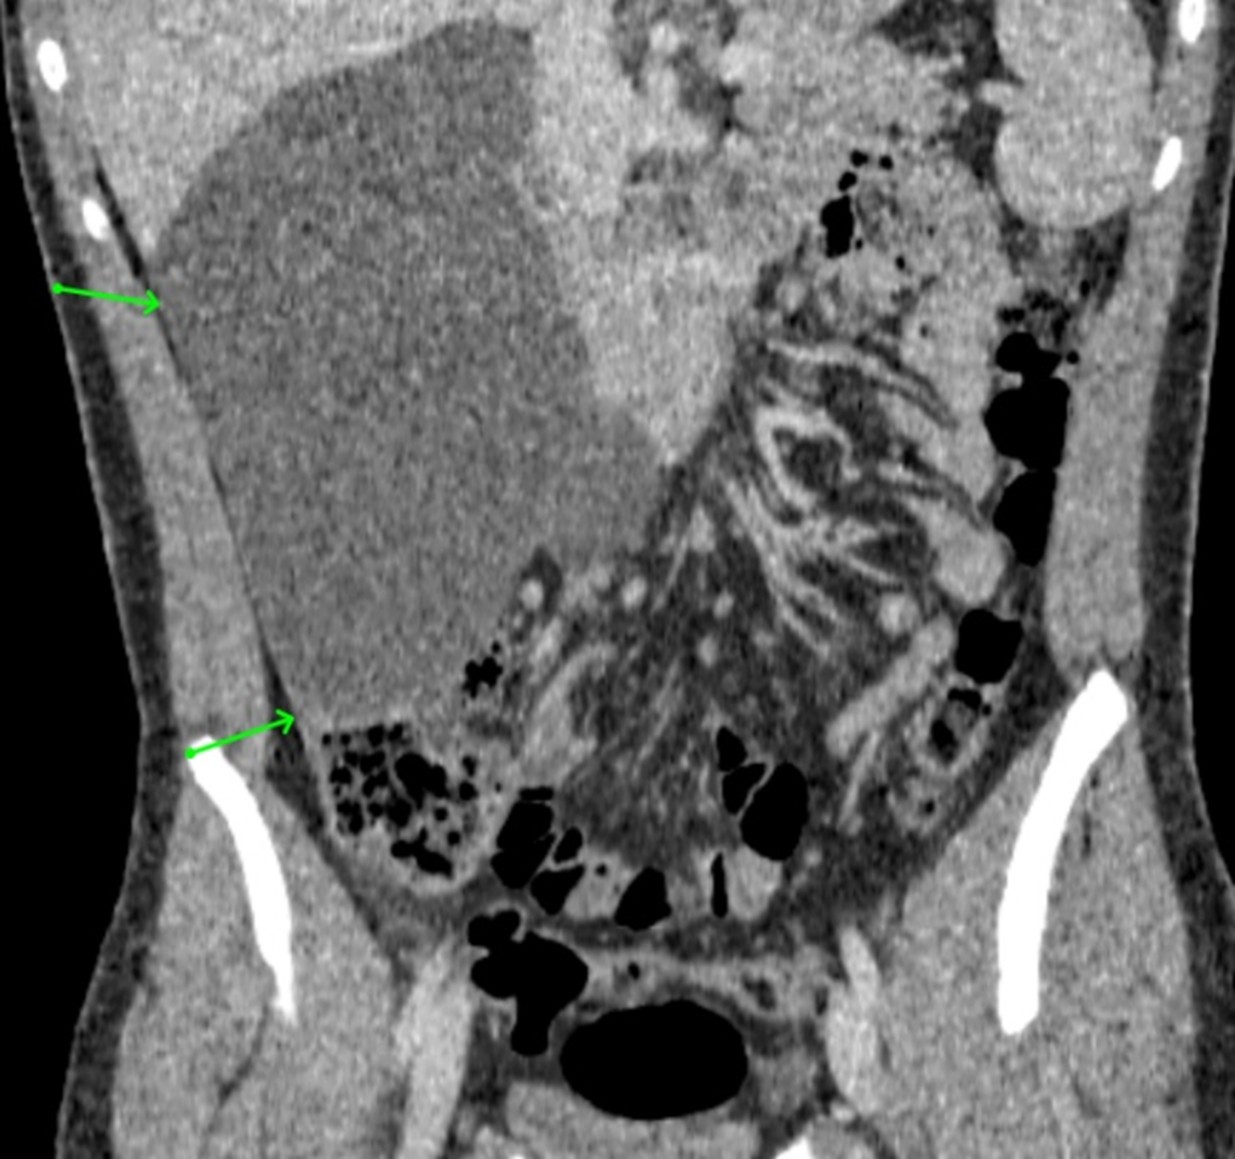

Primary Hepatic Leiomyosarcoma - A Rare Neoplasm with Diagnostic and Therapeutic Challenges

João Kleber de Almeida Gentile, Beatriz Terezinha Franco Renesto, Eloíza Helena Dias Quintela, Alexandre Sacchetti Bezerra, Flavia Magella, Luís Fernando Alves Miléo, Daniel de Castilho da Silva, Ronaldo Modesto de Souza Filho, André Cosme Oliveira